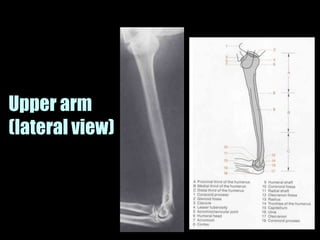

This document provides an overview of normal musculoskeletal imaging. It discusses basic x-ray concepts and densities. It then reviews normal anatomy as seen on x-rays of the skull, spine, pelvis, chest, and extremities. Key anatomical structures are labeled on example x-rays for the shoulder, hip, knee, and foot. Quizzes are included to test recognition of anatomical structures and patient age based on x-rays.